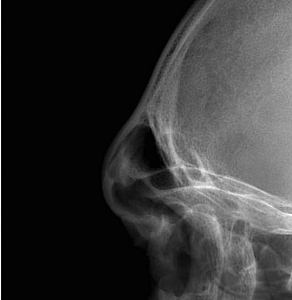

- CT imaging is often obtained preoperatively to assess sinus size and the thickness of the obverlying bone of the nedial brow prominences. The lateral or tail of the brow is always solid bone.

- Many prominent male brow ridges cannot be safely reduced with shaving alone.

- In those cases, setback produces a much more noticeable contour change.